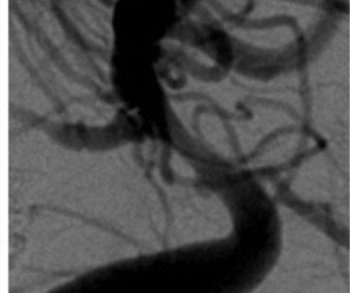

Emphasizing the proper diagnostic characterization of sidewall aneurysms, the authors of a new study found no significant differences in occlusion status or complications when they compared the approved use of intrasaccular flow disruption for bifurcation aneurysms to off-label treatment of sidewall aneurysms.